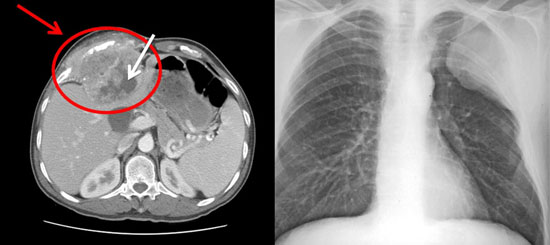

Chest Wall Cancer

Primary chest wall cancers are a large group of benign or malignant tumors, which are originated from cortex, bone, cartilage and soft tissues in thorax. Spreads in the chest wall can stem from lungs, pleura, muscles, or breast cancer. These might be distant spreading or more often local involvement. Various non-cancer diseases might also spread…